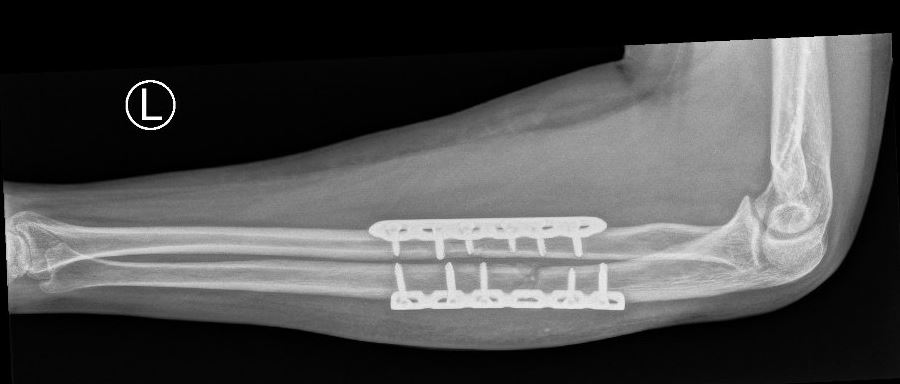

Operatie

In het geval dat zowel uw spaakbeen als uw ellepijp gebroken is, is het meestal nodig beide breuken vast te zetten. Meestal worden de afzonderlijke breuken vastgezet met behulp van een plaat en schroeven in het bot. Afhankelijk van de plaats van de breuk en de voorkeur van uw traumachirurg, kan dit via 2 kleinere sneden of via 1 grotere snede. Indien er sprake is van een ernstig weke delen letsel kan uw chirurg er ook voor kiezen om de breuken, al dan niet tijdelijk, van buitenaf vast te zetten met een extern fixatie mechanisme (de zogenaamde ‘externe fixateur’). Welke operatie u krijgt, is afhankelijk van de eigenschappen van de breuk en de toestand van de huid en de spieren. Uw traumachirurg bepaalt ook of het nog nodig is om na de operatie nog tijdelijk gips te krijgen voor extra stevigheid of rust.